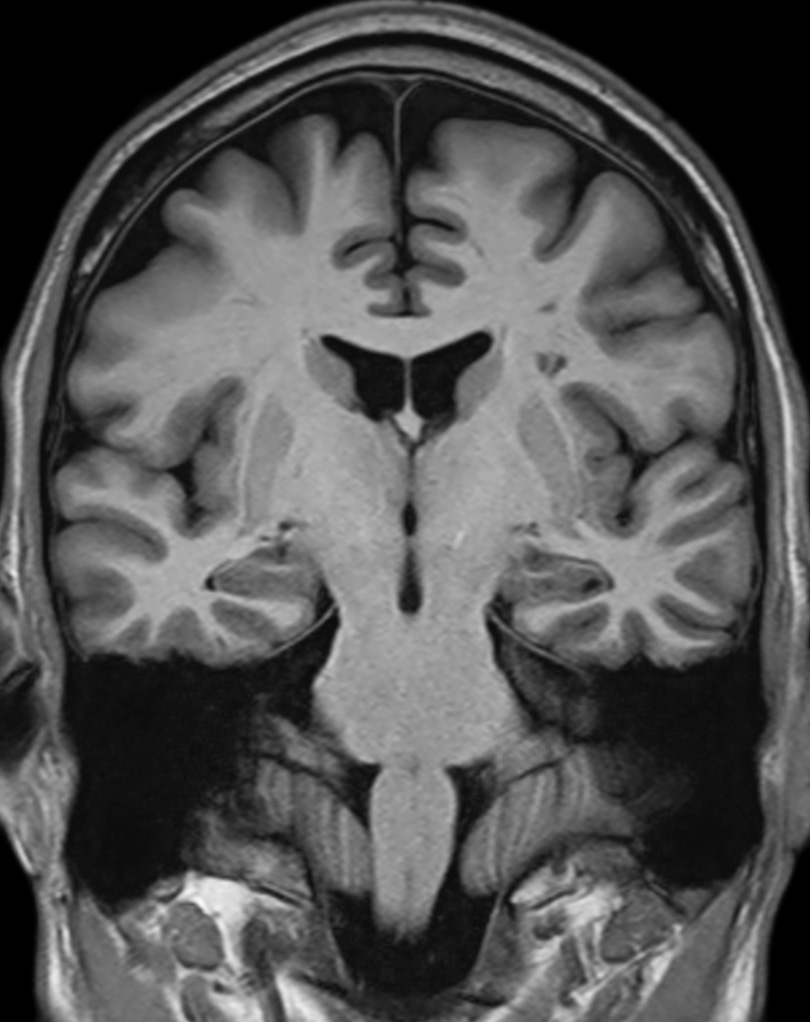

Hippocampus